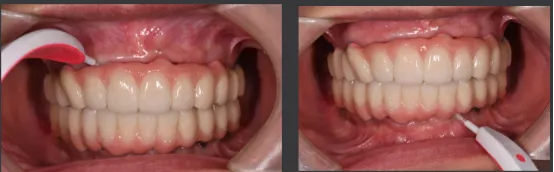

· 口内pick-up 固定临时修复体,患者上下颌咬合关系良好。

· 第一幅临时修复体戴入4个月后,种植体周围软组织健康,15.25行种植二期手术。

· 口扫获取种植体周围软组织及咬合关系信息。

· 数字化设计第二幅临时修复体,PMM切削,上下颌各修复12个单位的修复体,16.26单端桥设计

· 第二幅临时修复体戴入口内,修复效果良好,前伸侧方咬合无干扰,预留清洁通道。

· 修复体红白美学满意,前伸侧方咬合均无干扰,前牙前突问题解决,指导患者清洁。